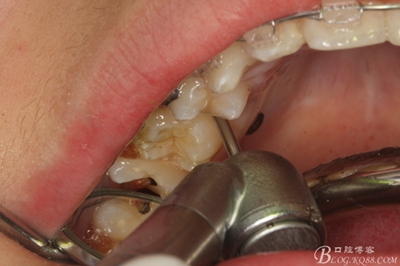

圖8.因16與14合面的間隙僅2mm左右,牙根無法合向脫位,如何考慮15牙根的脫位將是最大問題。高速手機去除牙間隙內(nèi)的覆蓋在15牙根表面的牙齦組織

圖10.去除牙齦組織后。露出15牙根斷面,合面無法脫位